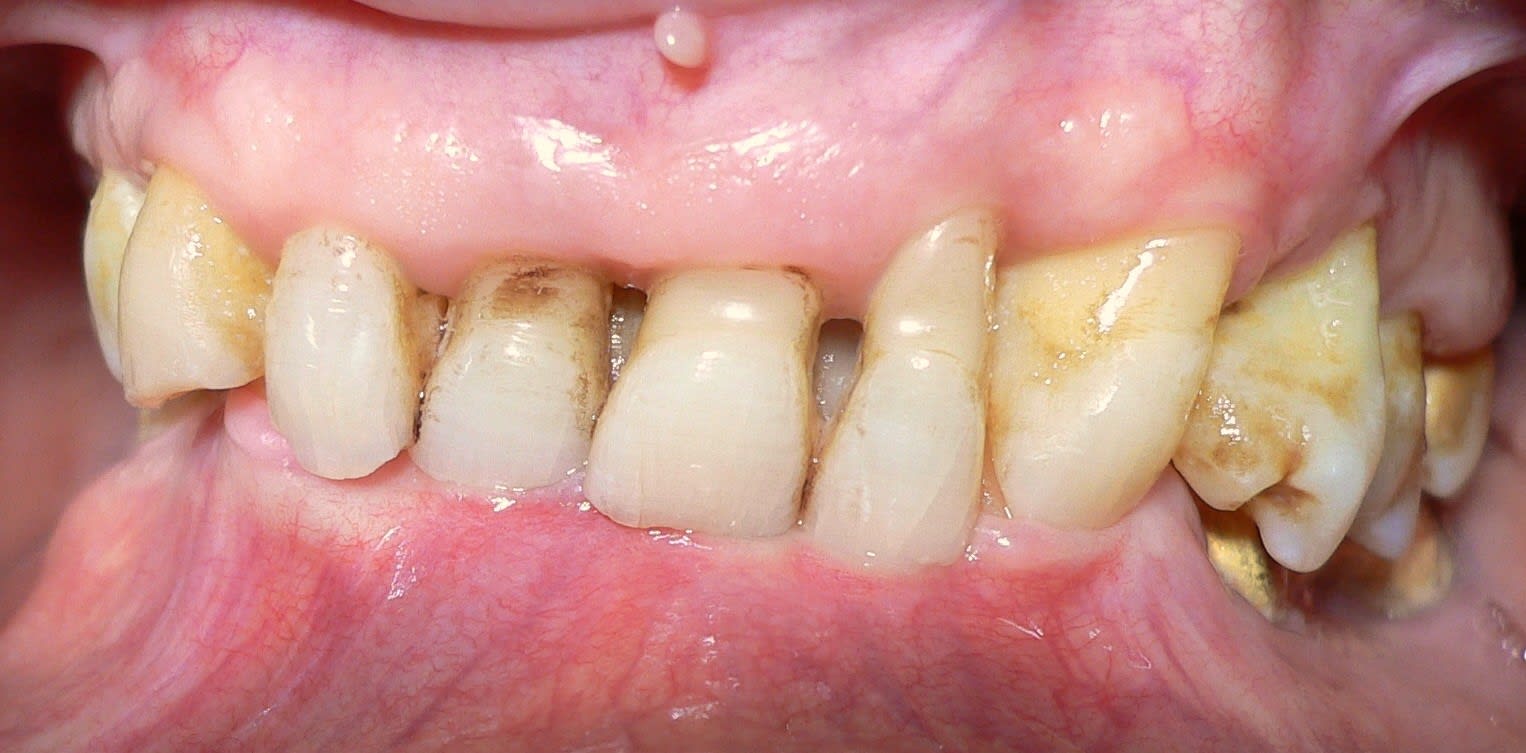

Faut voir, mais sur la photo de face entre les Ic centrales on voit qu'il ne doit pas y avoir plus de 2 mm entre les crètes du haut et du bas. Moi j'appelle ça une perte de DV. A la rigueur une DV trop faible si on pense qu'elle est comme ça depuis toujours mais j'en doute, les molaires semblent quand même sous le plan d'occlusion.